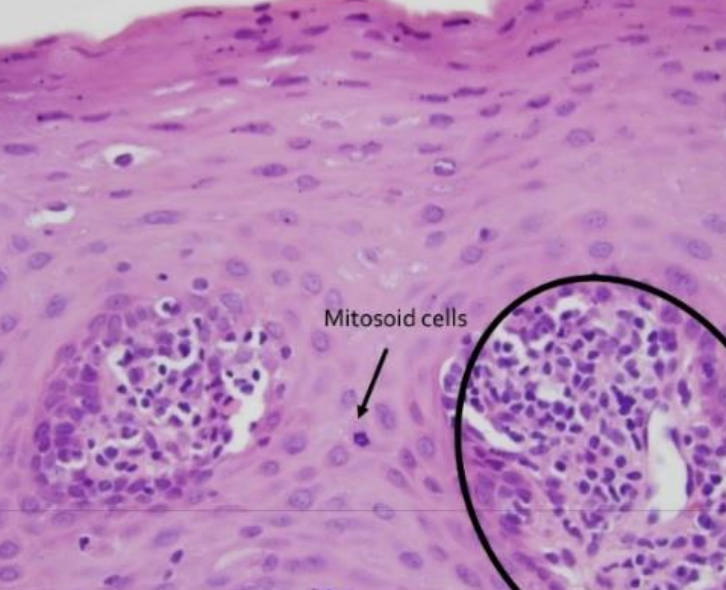

| Multifocal epithelial hyperplasia (Heck’s disease, 13, 32) |

低社經、HIV | 唇、頰、舌 | 小、軟、多、無痛 | |||

Papillomatous variant

|

Papulonodular

|

|||||

|

||||||